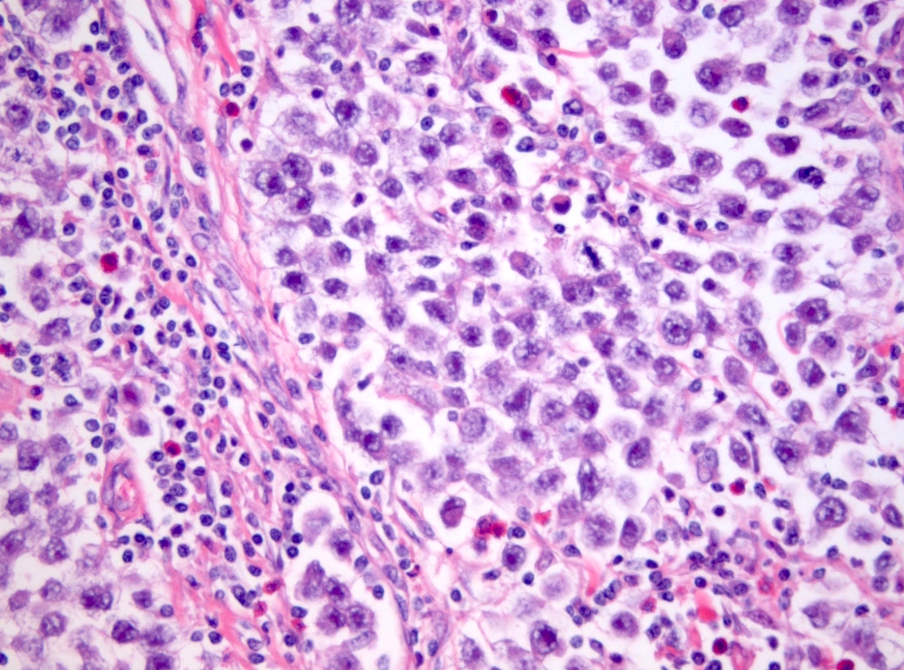

59M. Testicular mass

Dx?

Key features?

Dx: Spermatocytic tumour

Incidence peaksin the the sixth decade of life, with a mean age of 52–59 years. The tumours are rare in teenage boys and non-existent in children.

The most characteristic feature is a polymorphous cell population, often described as tripartite, consisting of three distinct cell types with distinguishing features based on cell size and chromatin: the small cells exhibit round, uniformly dense nuclei and scant cytoplasm; intermediate-sized cells have round nuclei with finely granular to filamentous (spireme) chromatin and variably prominent nucleoli; and giant cells have single or multiple nuclei with similar nuclear features to those of the intermediate-sized cells. Mitotic figures, including atypical forms, are usually frequent, as are a large number of apoptotic tumour cells. Unlike in a classic seminoma, prominent lymphocytic infiltrates are not present, and granulomatous inflammation is only rarely seen. Intratubular growth is common, but GCNIS is absent.

Essential: spermatocytic tumours typically occur in an older age group, with most patients in their fifth or sixth decade; tripartite microscopic appearance with three distinct cell types and without lymphocytic infiltrate or prominent fibrous septa; no immunoreactivity for usual embryonic germ cell tumour markers; no GCNIS.